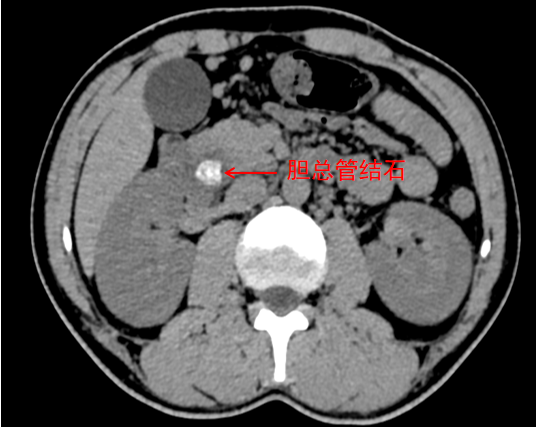

患者熊先生有着多年的地中海贫血病史,早在2019年,就因脾功能亢进做过腹腔镜脾切除术。该院肝胆胰外科主任曹庭加介绍,地中海贫血患者会出现长期溶血的情况,进而导致胆红素代谢紊乱,很容易形成胆色素结石。再加上患者之前做过脾脏切除手术,腹腔内存在粘连,大大增加了此次胆道取石手术的难度。但胆总管结石引发的胆管炎,会造成胆汁淤积,持续损伤肝脏,及时解除梗阻、控制炎症已是当务之急。

患者术前影像

结合患者年纪轻、胆囊功能完好、胆囊内泥沙样结石量少的身体状况,加上患者本人强烈的保胆意愿,医院团队专门开展多学科会诊评估,量身制定了个性化手术方案。手术中,医生采用腹腔镜联合胆道镜,精准取出胆总管内的结石,再用胆道子镜细致清理胆囊里的泥沙样结石,同时配合胃镜完成胆道探查,通过腹腔镜、胆道镜、胃镜三镜联合的全程可视化操作,实现了精细化、零损伤的手术操作。